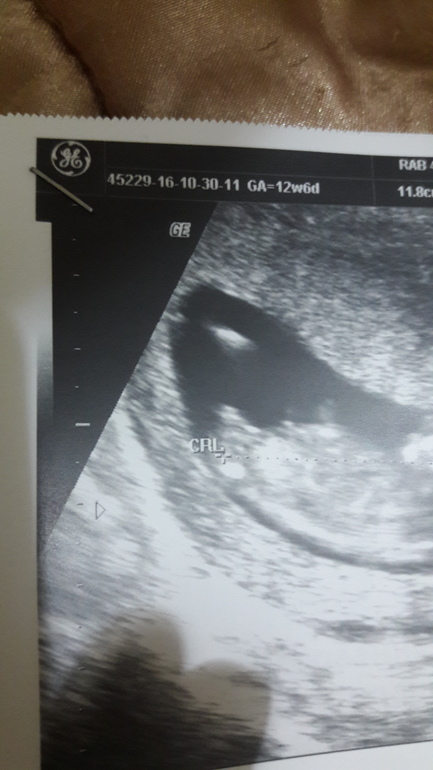

А вот и нет, на таком сроке в профиль, но в другом срезе.

Вот так смотрят бугорок на 1 скрининге .